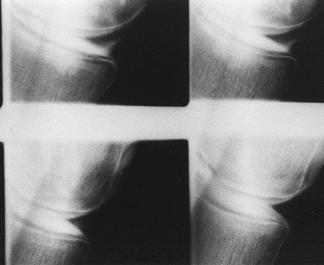

intra-articularly, and then obtaining radiographs in multiple

projections, both with and without stress applied to the knee (Fig. 84.18).

Although arthrography has been largely replaced by MRI, the former

technique may be indicated in patients with contraindications to MRI.

The primary reason for obtaining a knee arthrogram is for assessment of

the menisci (2).

Figure 84.18. Arthrogram demonstrating a tear of the posterior horn of the medial meniscus.

collateral ligament injuries, OCD, chondral defects, plica, and

popliteal cysts. The accuracy of arthrograms for the diagnosis of

meniscal tears has been reported to be between 76% and 96% (13,28). In comparison to MRI, there are more false-negative results associated with the use of arthrography.